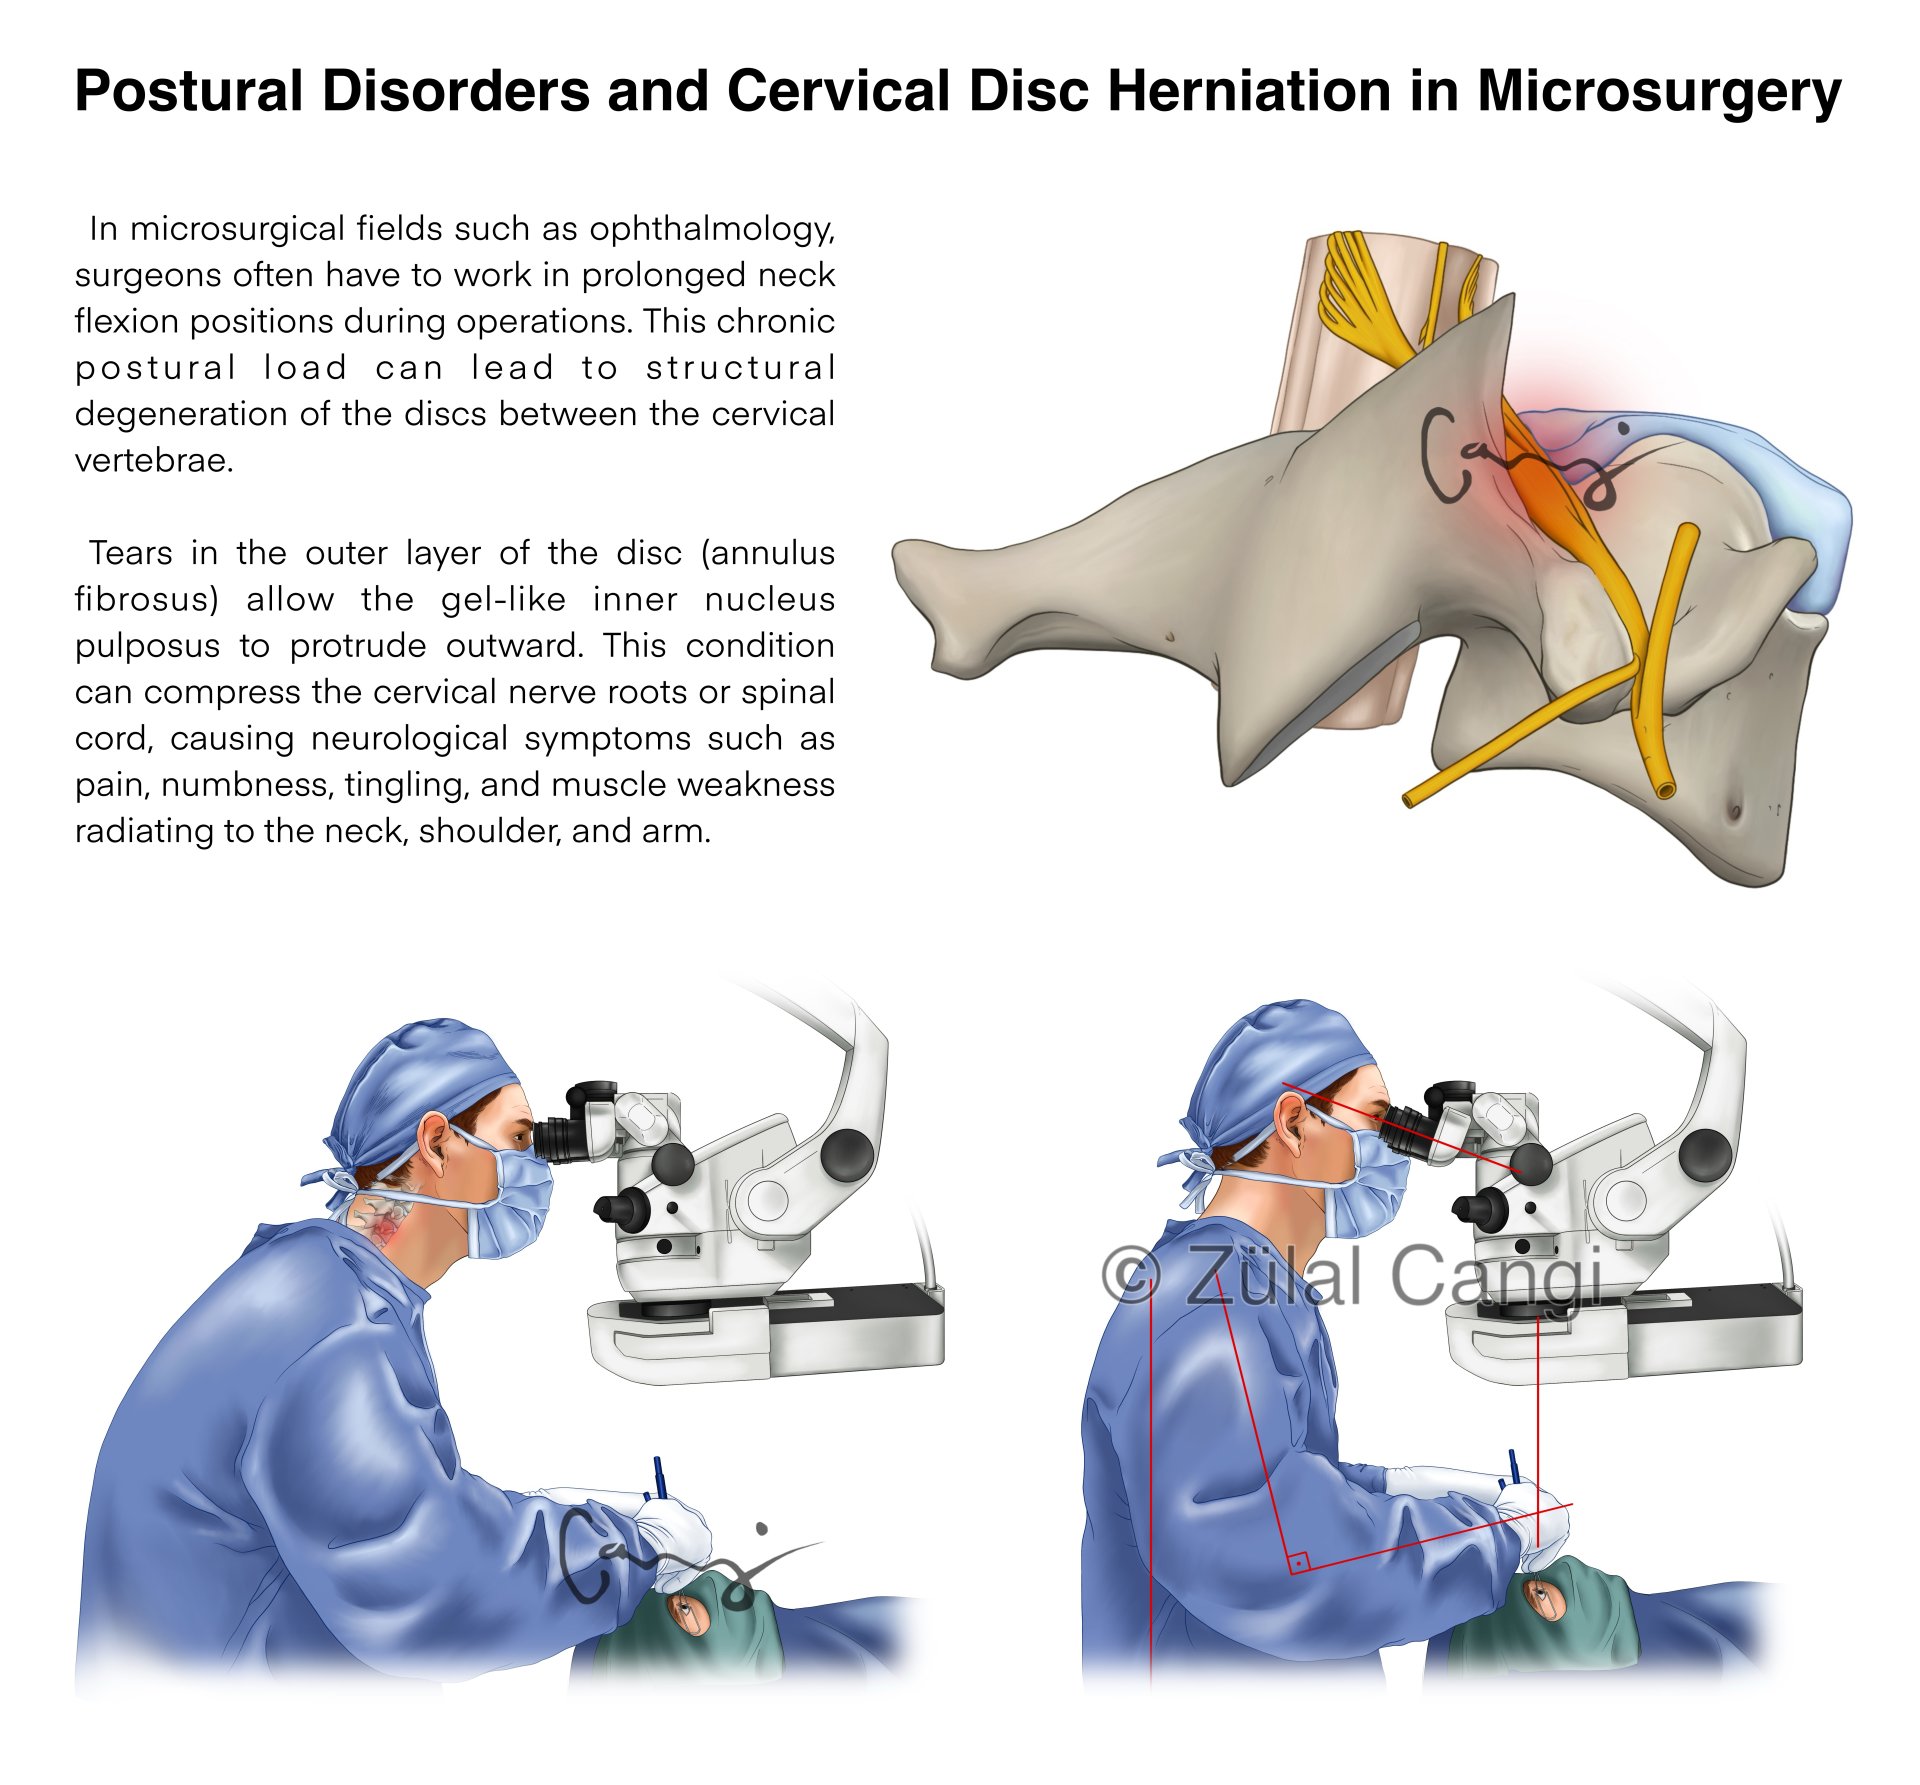

Sanatın estetiğini bilimin kesinliğiyle bir araya getiren Zülal Cangi, medikal ve bilimsel illüstrasyon alanındaki çalışmalarıyla akademik yayınlar, eğitim materyalleri ve çeşitli bilimsel platformlar için görsel içerikler üretmektedir. Amacı, bilimsel bilgiyi yalnızca doğru biçimde aktarmakla kalmayıp, aynı zamanda öğretici ve estetik bir dille görünür kılmaktır.

PORTFÖY